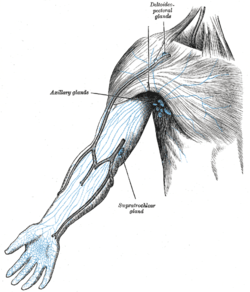

Lymphatics of the arm